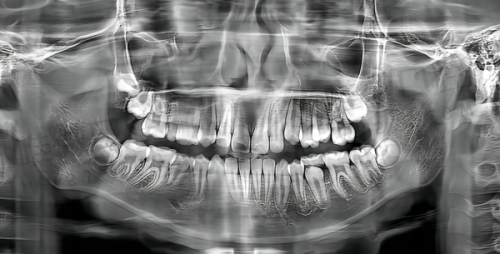

医院整体面积有千余平米,宽敞的候诊区、独立诊室和舒适的诊疗椅应有尽有。重点是,这里不仅环境干净,还配备了德国西诺德综合治疗椅、3D口腔CT、数位化导板系统等精良设备,为各种精密种植、全景拍片、隐形矫正等复杂项目提供精细保护。

金平院配备了3D导板、数字印模仪等设备,尤其在“All-on-4”全口即刻种植领域表现突出,大大提升种植效率和舒适度,深得老年群体喜欢。

同样,这里也使用了德国进口数字X光机、光学扫描设备和种植计划系统,可以大幅提升诊断正确率和治疗舒适程度。尤其在儿童口腔、早期咬合干预方面特别值得信赖。